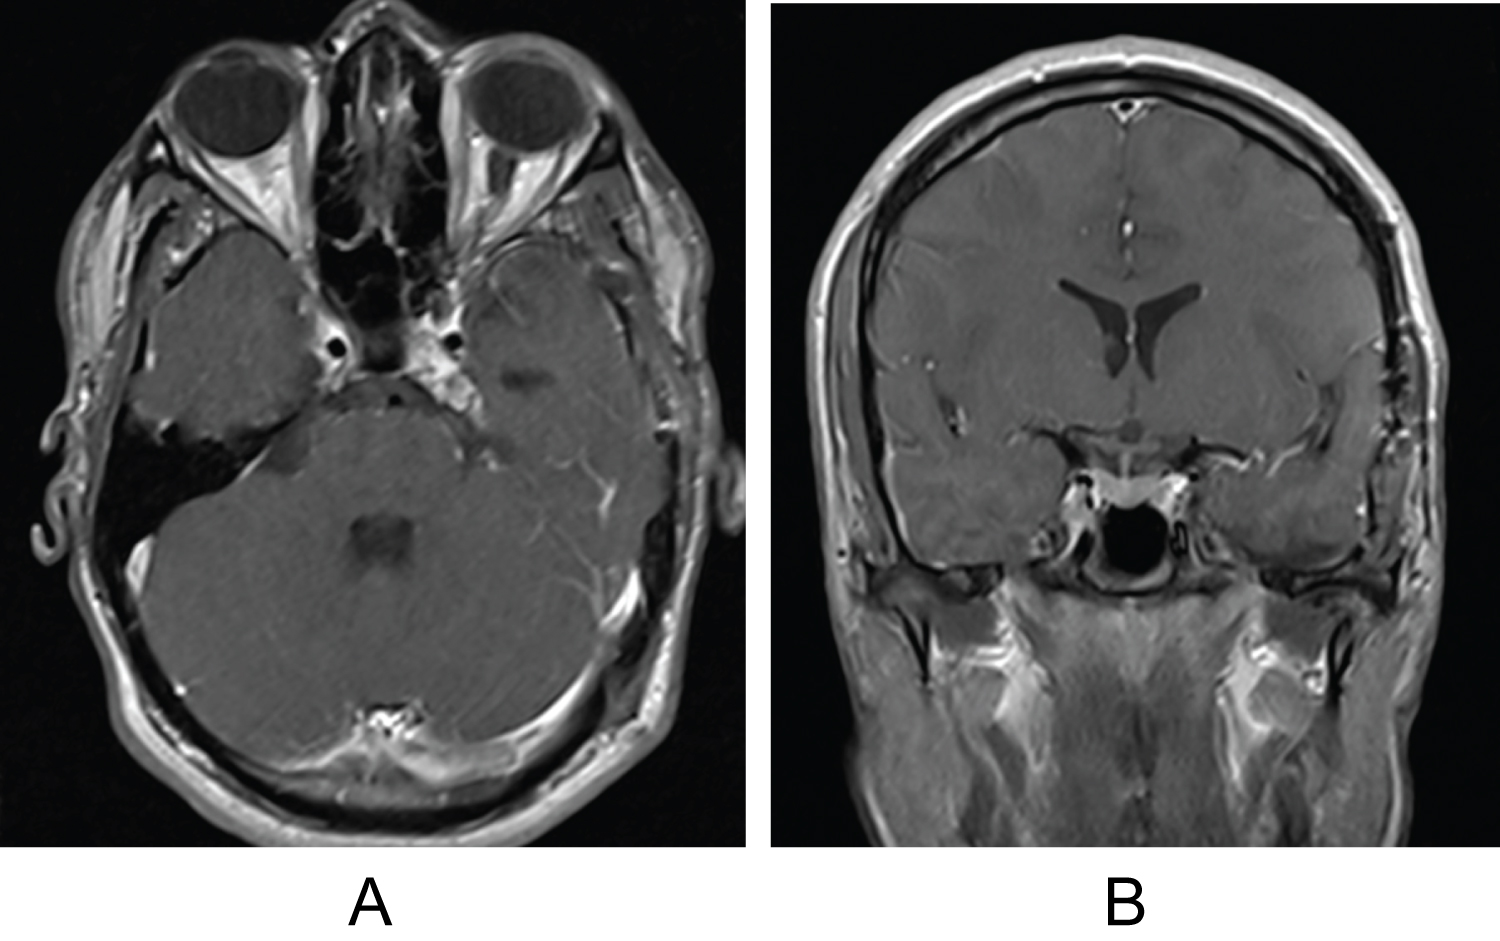

An 18-year-old male with no significant past medical history presented with a three week history of worsening left monocular diplopia and compensatory head tilt. Five months prior to presentation left sided neglect was noted by his father. He denied any associated symptoms including headaches, nausea, fatigue, bone/back/neck pain, or changes in cognition/speech/hearing. Initial neurological examination revealed left abducens nerve palsy and partial left trochlear nerve palsy, as well as anisocoria with left pupil larger than the right. The patient underwent brain and orbital magnetic resonance imaging (MRI) revealing a 27.3 × 29.0 × 18.6 mm left cavernous sinus mass arising from the petrous apex with extension into the cavernous sinus and the Dorello's canal; such findings are consistent with the presenting symptoms (Figure 1A and Figure 1B). The CT scan confirmed a calcified mass (Figure 2A and Figure 2B). Patient was hospitalized and scheduled for resection of the left cavernous sinus.

Figure 1: (A,B) Pre-operative axial and coronal brain MRI imaging using T1 sequence with contrast shows the heavily enhancing mass arising from the left cavernous sinus with mass effect on mesial temporal lobe and displacement of the ICA artery. View Figure 1